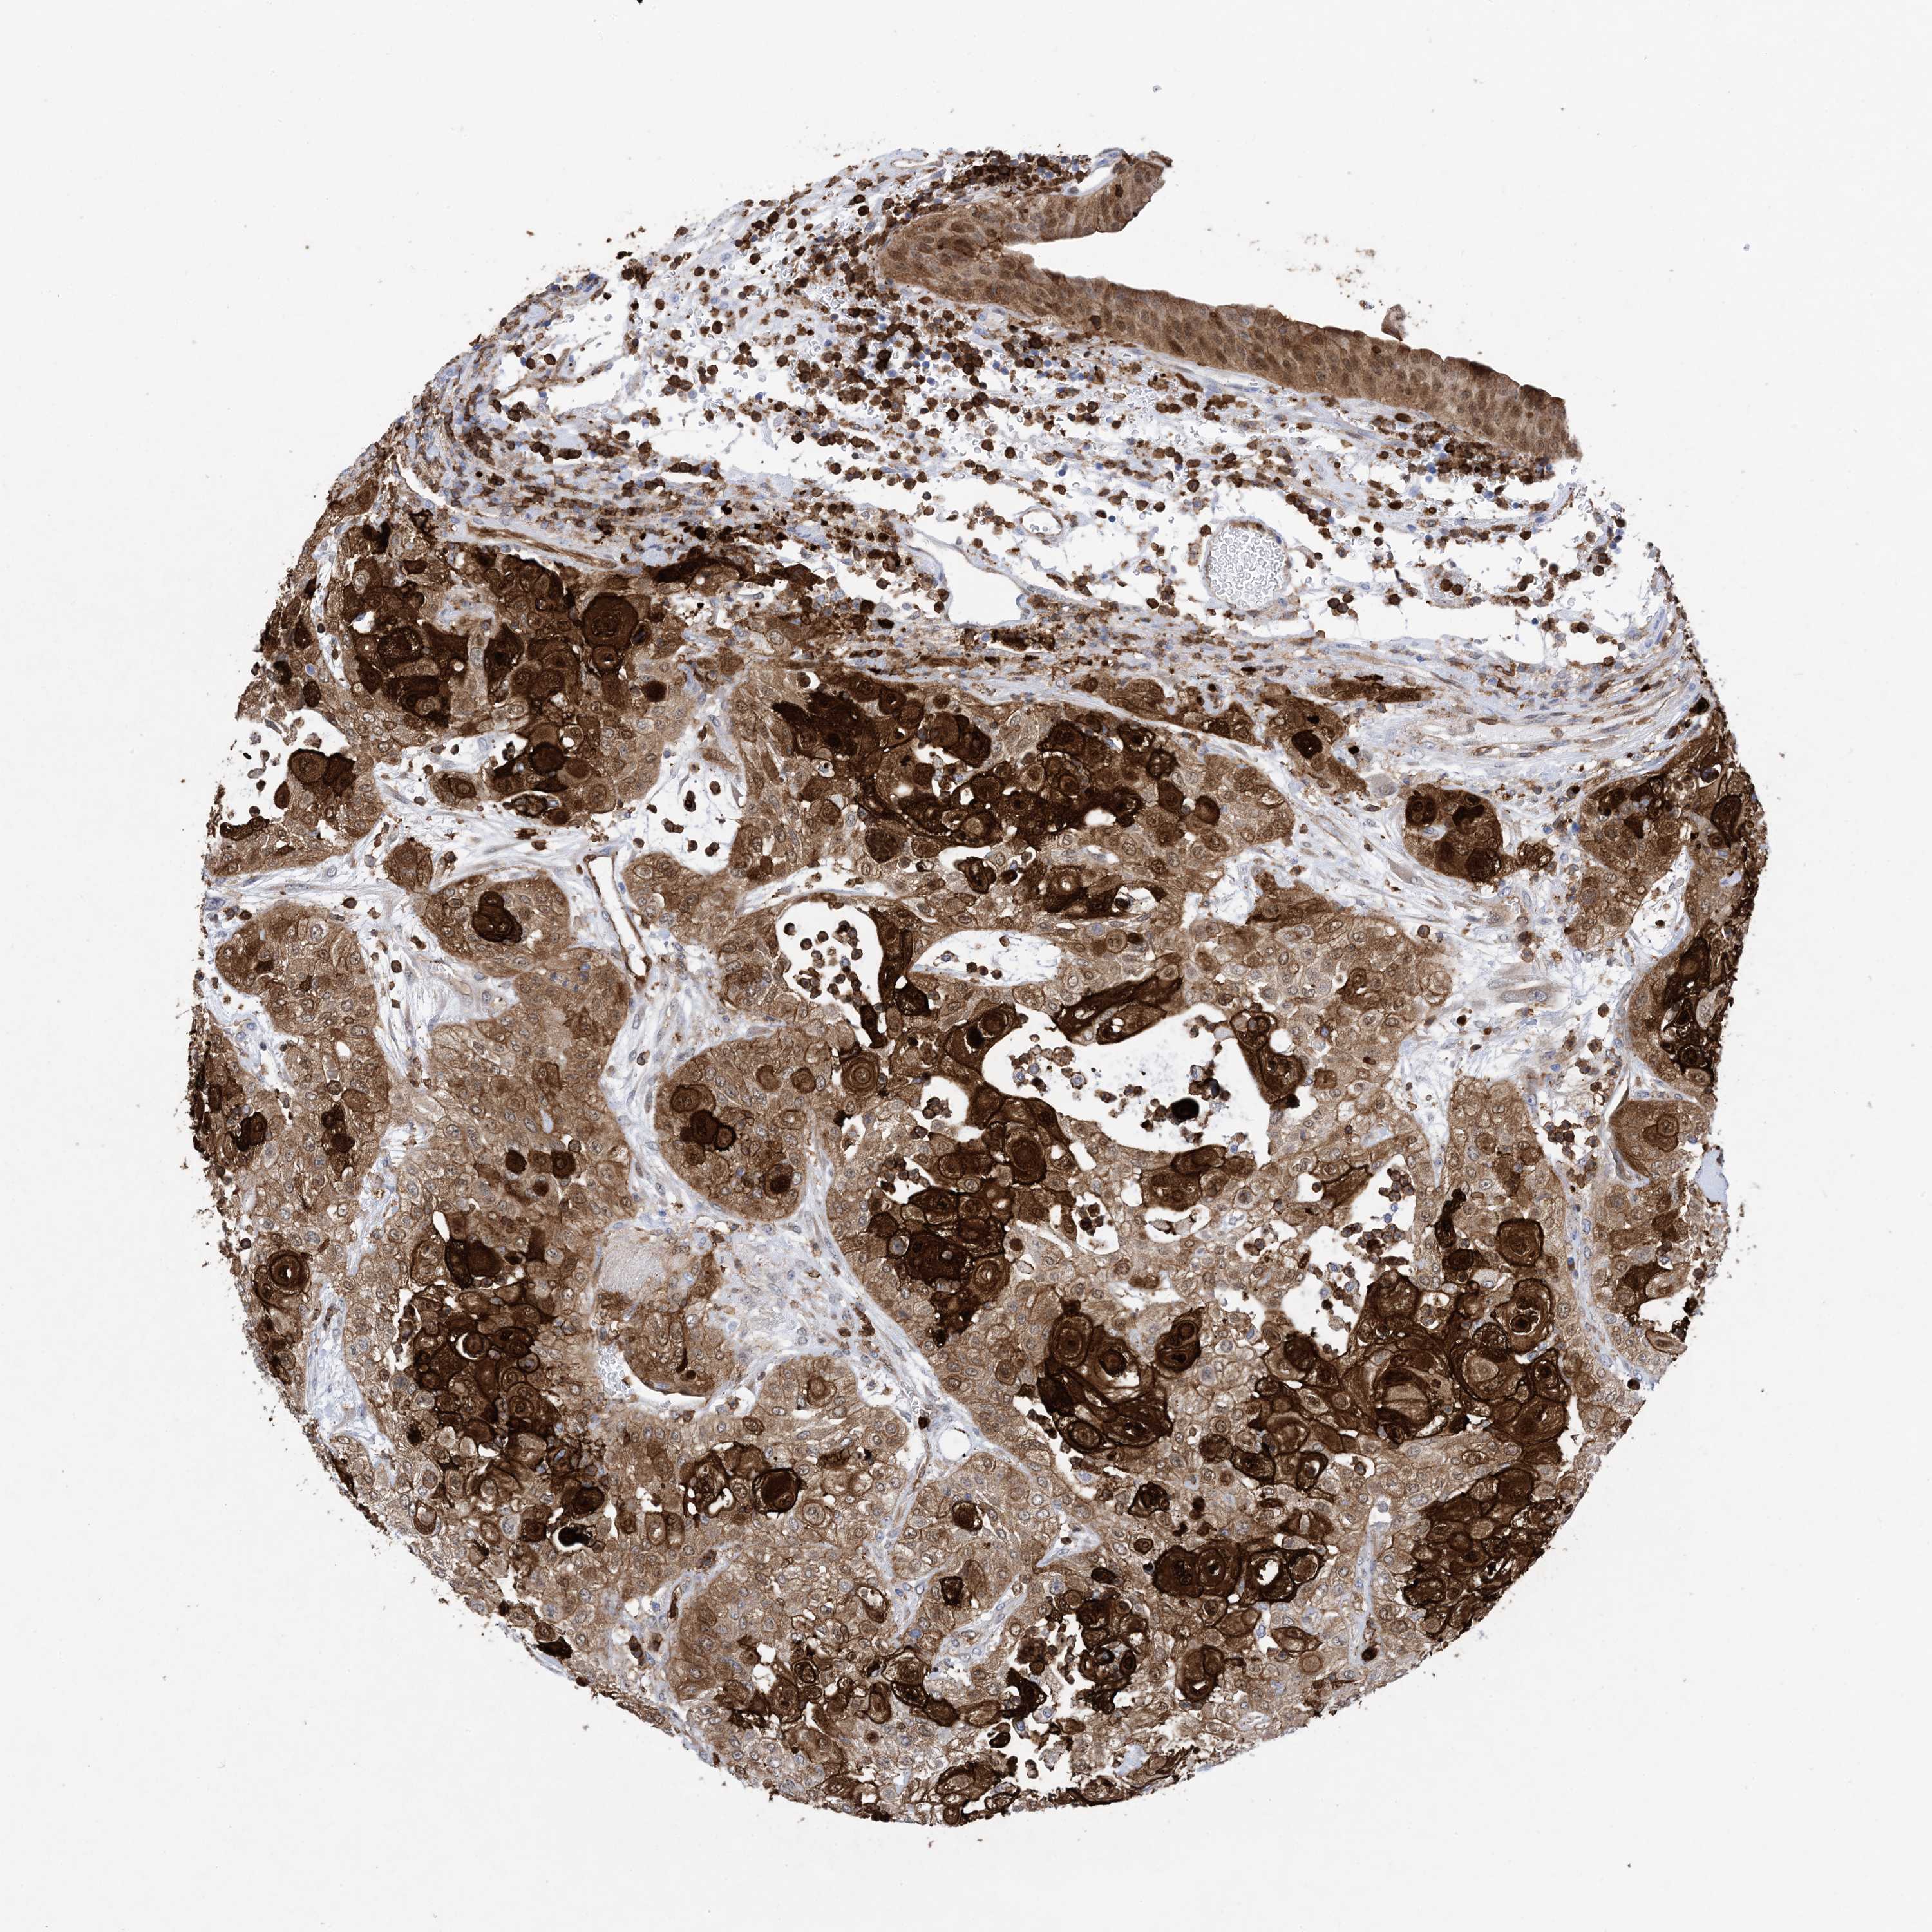

UROTHELIAL CANCER - Protein expressioni

A mouse-over function shows sample information and annotation data. Click on an image to view it in a full screen mode. Samples can be filtered based on level of antibody staining by selecting one or several of the following categories: high, medium, low and not detected. The assay and annotation is described here.

Note that samples used for immunohistochemistry by the Human Protein Atlas do not correspond to samples in the TCGA dataset.

Antibody stainingi

Antibody staining in the annotated cell types in the current human tissue is reported as not detected, low, medium, or high, based on conventional immunohistochemistry profiling in selected tissues. This score is based on the combination of the staining intensity and fraction of stained cells.

Each image is clickable and will lead to virtual microscopy that enables deeper exploration of all samples and also displays staining intensity scores, fraction scores and subcellular localization as well as patient and tissue information for each sample.

HPA011271

HPA011272

CAB013023

CAB035987

CAB058693

CAB080415

Staining

High

Medium

Low

Not detected

Intensity

Strong

Moderate

Weak

Negative

Quantity

>75%

75%-25%

<25%

None

Location

Nuclear

Cytoplasmic/membranous

Cytoplasmic/membranous,nuclear

Urothelial carcinoma, High grade